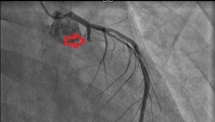

Chàng trai 25 tuổi nhồi máu cơ tim vì hút 20 điếu thuốc lá mỗi ngày

Mới đây, các bác sĩ Bệnh viện Nhân dân 115 (TP.HCM) vừa cấp cứu cho nam bệnh nhân bị nhồi máu cơ tim cấp khi chỉ mới 25 tuổi.